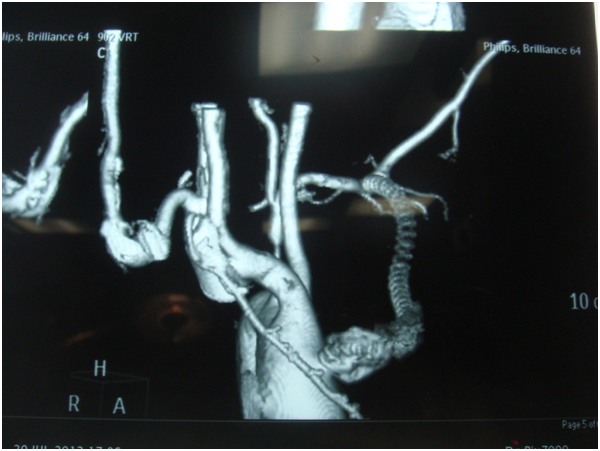

A 55 years old gentleman came to our hospital with discharging chest wound with occasional bleeding through upper chest wound. He was also suffering from fever occasionally. One and half years back he was operated in another hospital with CABG with Aorto-axillary bypass. On 4th postoperative day he needs reopening for mediastinal bleeding and needed a long ICU stay. Then he developed above mentioned symptoms. 5 days back he developed severe bleeding and was treated conservatively in another hospital. After admission CT angiogram was done-showed-Aorto-axillary bypass graft penetrating sternum and developed a leak in the aortic side. We decided for urgent operation on next day on 1.08.13-we went to femoro-femoral bypass first [1].

Figure 1: Aorto-axillary bypass-leak in aneurysmal aortic end.

Figure 2: Aorto-axillary bypass-showing leak and eroding sternum.